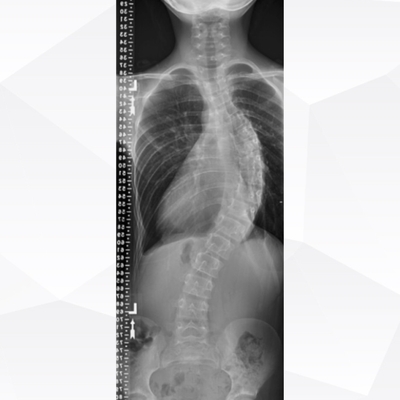

Click on an image below to view more info.